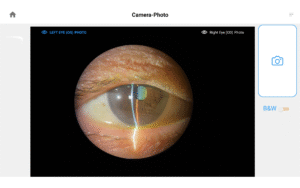

Illuminate your exams and transform patient engagement like never before. When patients see detailed images of their eyes, they gain a deeper understanding of their health and recognize the importance of compliance and follow-up care. Throughout development, our team saw firsthand the profound impact of imaging in the clinic—watching patients smile, express genuine appreciation, and embrace their health journey. That unforgettable experience remains the most rewarding part of our work.

Pushing ahead, our imaging system includes our new, patent-pending Halo background light. Working with native slit lamp illumination, Halo delivers unparalleled clarity of the ocular adnexa. You’ll uncover details of the meibomian glands, acinar spaces, conjunctiva, lid margins, and lashes like never before.

CPT / HCPCS Code 92285 External ocular photography with interpretation and report for documentation of medical progress, (eg close-up photography, slit lamp photography, goniophotography, stereo photography).